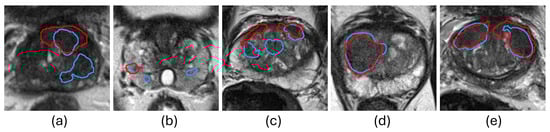

5.1.3. Lesion-Level Analysis